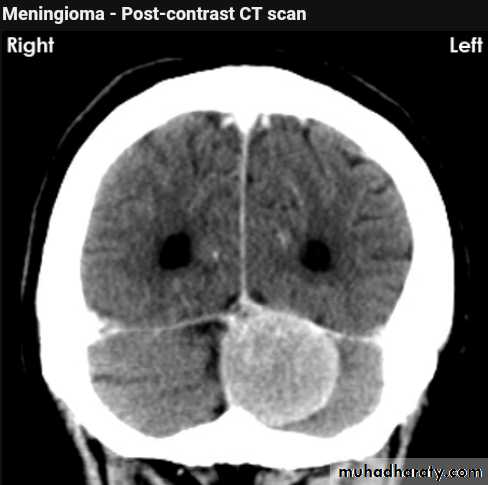

CT finding

meningioma presented as isodense area or slightly hyper density area with surrounded crescent of hypo density ( csf cap ) post contrast injection the lesion enhance homogeneously with enhancing Dural tail .

20 % show calcification

hyperostosis & thickening of the near by bony part of the skull & diplioc space .

it may be associated with little or no peri focal edema .